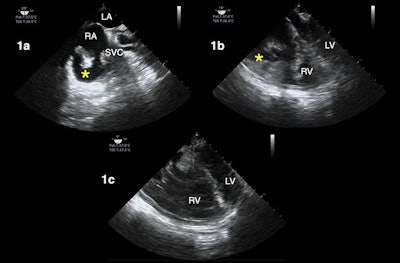

TEE can also be used to image patients' lungs from within their esophagus, also known as transesophageal lung ultrasound (TELUS). This version of lung ultrasound may work particularly well for certain types of patients, such as obese individuals, those with surgical dressing, or those experiencing subcutaneous emphysema, the authors noted.

Other use cases for TEE include evaluating the heart and lungs of patients who must stay in a prone position and those experiencing shock, a finding not uncommon in hospitalized patients with COVID-19, according to the authors.

"We have found that the TEE exam in prone patients has been particularly helpful during the COVID pandemic, given the degree of hypoxemia seen in these patients and the many urgent ECMO evaluations we've had to perform," the authors wrote.